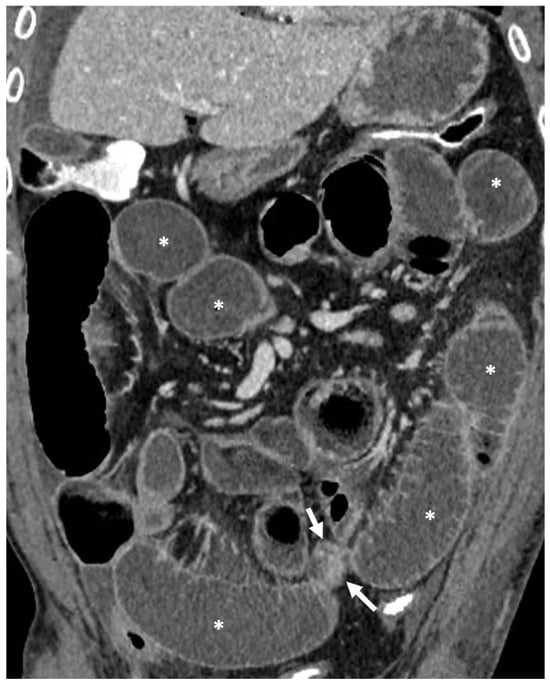

- A normal bowel loop caliber ranges between 2 and 2.5 cm. A bowel lumen is dilated when it has a maximum diameter greater than 2.5–3 cm. The dilation is mild when the upstream lumen is dilated up to 4 cm and severe when it is more than 4 cm (Figure 3) [24]. Pre-stenotic bowel dilatation should always be checked, as it is a sign related to bowel obstruction. Moderate to severe stenosis was determined via double-contrast imaging (conventional barium study) with a sufficient amount of injected air, and stenosis was defined as stenosis in which the lumen was less than one half that of neighboring healthy intestine [25].